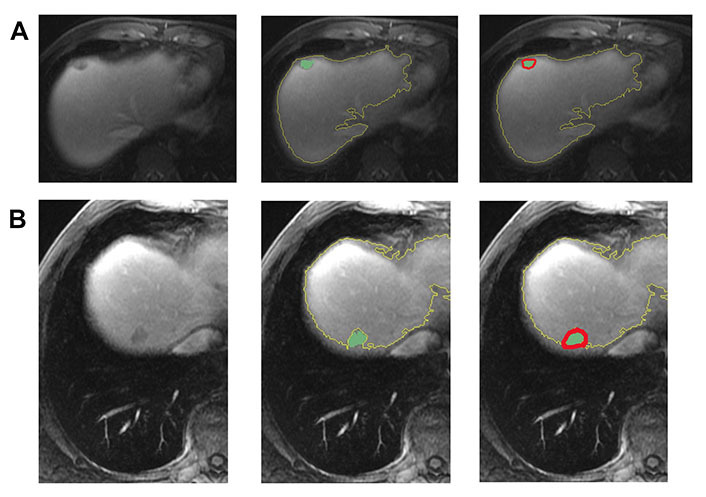

Methods: From 2007-2015, forty-eight patients who underwent MRI within 3 months prior to initiating treatment for CRLM were identified. Clinicobiological prognostic variables were obtained from electronic medical records. Ninety-four metastatic hepatic lesions were identified on T1-weighted post-contrast images and volumetrically segmented. A total of 112 radiomic features (shape, first-order, texture) were derived from a 10 mm region surrounding each segmented tumor. A random forest model was applied, and performance was tested by receiver operating characteristic (ROC). Kaplan-Meier analysis was utilized to generate the survival curves.

Results: Forty-eight patients (male:female = 23:25, age 55.3 years ± 18 years) were included in the study. The median lesion size was 25.73 mm (range 8.5-103.8 mm). Microsatellite instability was low in 40.4% (38/94) of tumors, with Ki-ras2 Kirsten rat sarcoma viral oncogene homolog (KRAS) mutation detected in 68 out of 94 (72%) tumors. The mean survival was 35 months ± 21 months, and local disease progression was observed in 35.5% of patients. Univariate regression analysis identified 42 texture features [8 first order, 5 gray level dependence matrix (GLDM), 5 gray level run time length matrix (GLRLM), 5 gray level size zone matrix (GLSZM), 2 neighboring gray tone difference matrix (NGTDM), and 17 gray level co-occurrence matrix (GLCM)] independently associated with metastatic disease progression (P < 0.03). The random forest model achieved an area under the curve (AUC) of 0.88.

Conclusions: MRI-based peritumoral heterogeneity features may serve as predictive biomarkers for metastatic disease progression and patient survival in CRLM.